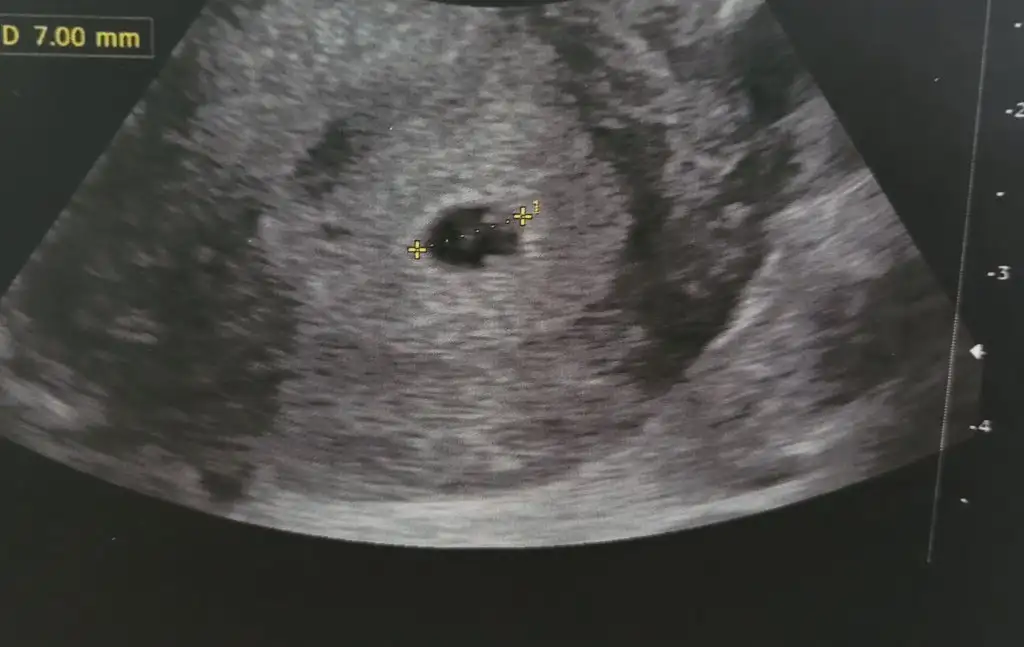

Şöyle çıktısı canm

Benimde siyah beyaz olan 5. Haftamın ultrasonu. Renkli olan dün acilde doktorun çektiği ultrason yani 7. Hafta. Kesede büyüme var ama yolk saçını görmedi. Çok huzursuz oldum.